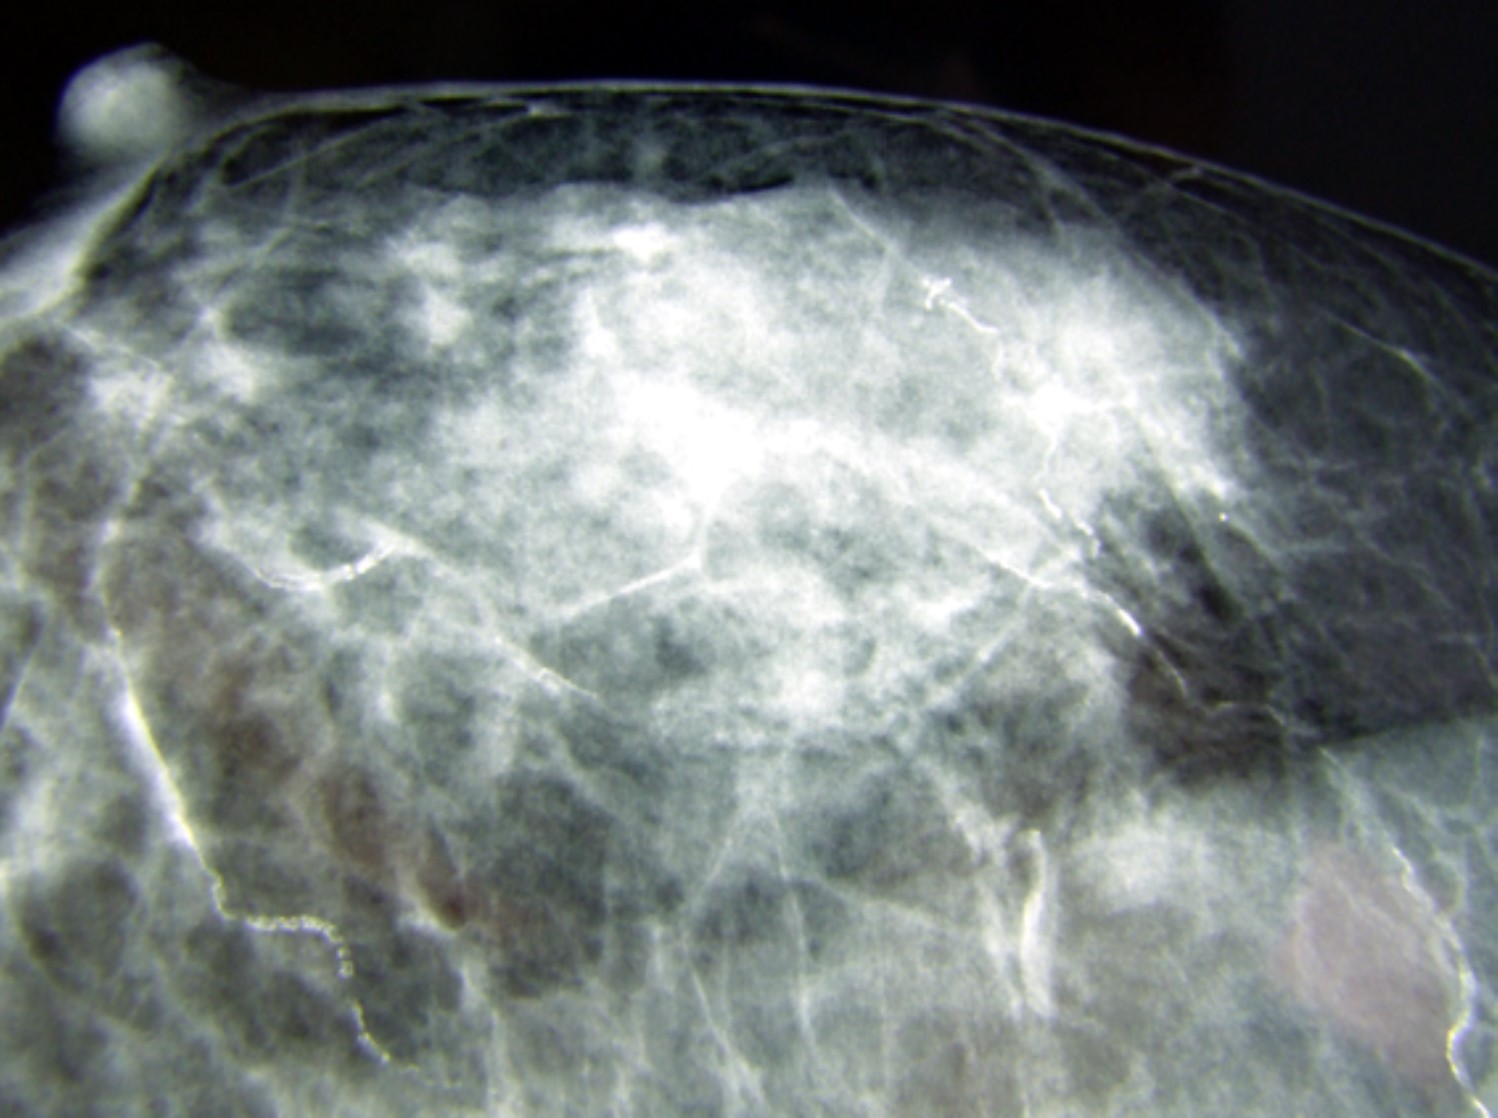

Mammographie nach 10 Jahren Einnahme von Hochdosis Kalziumtabletten.

Die verkalkten Adern sind deutlich zu erkennen.